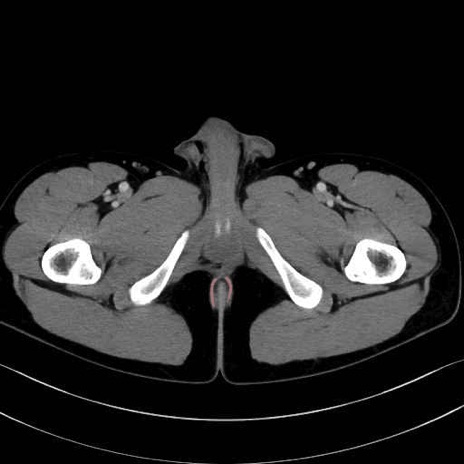

肛門挙筋 (Levator ani)